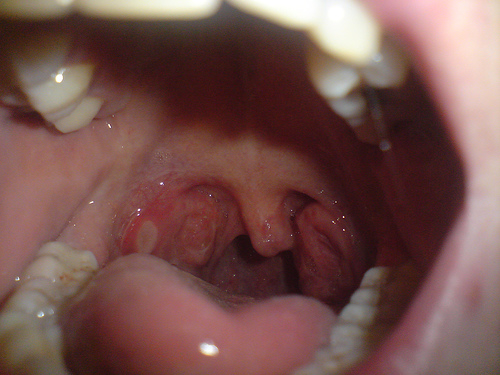

1. Úlceras orais (aftas): estas lesões estão quase sempre presentes. As aftas são o sintoma inicial em mais de dois terços dos pacientes. A maioria das crianças desenvolve múltiplas pequenas aftas indiferenciáveis das aftas ocasionais que são mais comuns.

Grandes aftas são mais raras, mas podem ocorrer, sendo muito difíceis de debelar.